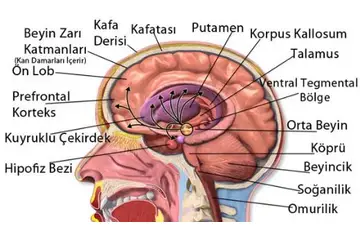

Beyin Dokusu Türleri ve Özellikleri

Beyin dokusu, merkezi sinir sisteminin temel yapı taşıdır ve iki ana türden oluşur: gri madde ve beyaz madde. Bu yapılar, bilişsel işlevler ve iletişim için kritik öneme sahiptir. Gri madde nöron hücre gövdelerini içerirken, beyaz madde aksonlarıyla iletişimi sağlar. Bu makalede, beyin dokusunun özellikleri ve sağlık üzerindeki etkileri detaylandırılacaktır.

Beyin Dokusu Türleri ve Özellikleri Beyin, merkezi sinir sisteminin en önemli organı olup, karmaşık yapısıyla birçok işlevi yerine getirmektedir. Beyin dokusu, genel olarak iki ana türden oluşmaktadır: gri madde ve beyaz madde. Bu makalede, beyin dokusu türleri ve özellikleri detaylı bir şekilde incelenecektir. Gri Madde Gri madde, beyin yüzeyinde yer alan ve nöron hücre gövdelerinin (soma) yoğun olarak bulunduğu bölgedir. Gri maddenin başlıca özellikleri şunlardır:

Beyaz Madde Beyaz madde, beyin içerisindeki nöronların aksonlarının yoğun olarak bulunduğu bölgedir. Aksonlar, nöronlar arasındaki iletişimi sağlamak için elektriksel sinyaller ileten uzun uzantılardır. Beyaz maddenin özellikleri şunlardır:

Beyin Dokusu Hücreleri Beyin dokusu, nöronlar ve glia hücreleri olmak üzere iki ana hücre türünden oluşmaktadır. Nöronlar, sinyalleri ileten ve bilgiyi işleyen temel hücrelerdir; glia hücreleri ise destekleyici işlevler üstlenir. Glia hücrelerinin türleri ve işlevleri şunlardır: